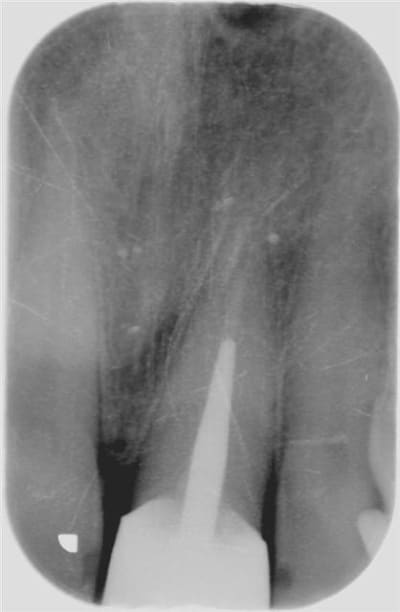

Allez, pour apporter mon caillou à la plage, un cas intéressant, d'implant en urgence.

consultation suite à une chute et fracture de 21 couronnée, un 29 Décembre, décision de poser l'implant le 31.12.

Extraction, mise en place d'un implant de 5*11.5 torque > 35N

Mise en place d'une dent provisoire transvisée.

Prothèse transvisée définitive à 3 mois.

Les 2 dernières photos à 1 an.

la photo ceram en place est à 6 mois. Noter l'amélioration des papilles entre 6 mois et 1 an...

non pas comblé pourtant hiatus assez important environ 1.5mm.

Longueur 11.5, mais j'aurais du mettre un plus long, pour la MCI j'aurais pris moins de risque...